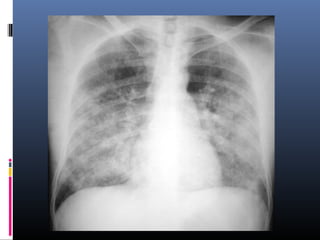

1. Edema pulmonar

 Infiltrado en

alas de

mariposa ó de

murciélago, por

edema

pulmonar.

 Líneas B de

Kerley.

 La fase siguiende del edema es la aparición

del edema alveolar, en el cual el aire de los

alvéolos se reemplaza por líquido de edema.

Este relleno produce la imagen de

distribución en “alas de mariposa”.